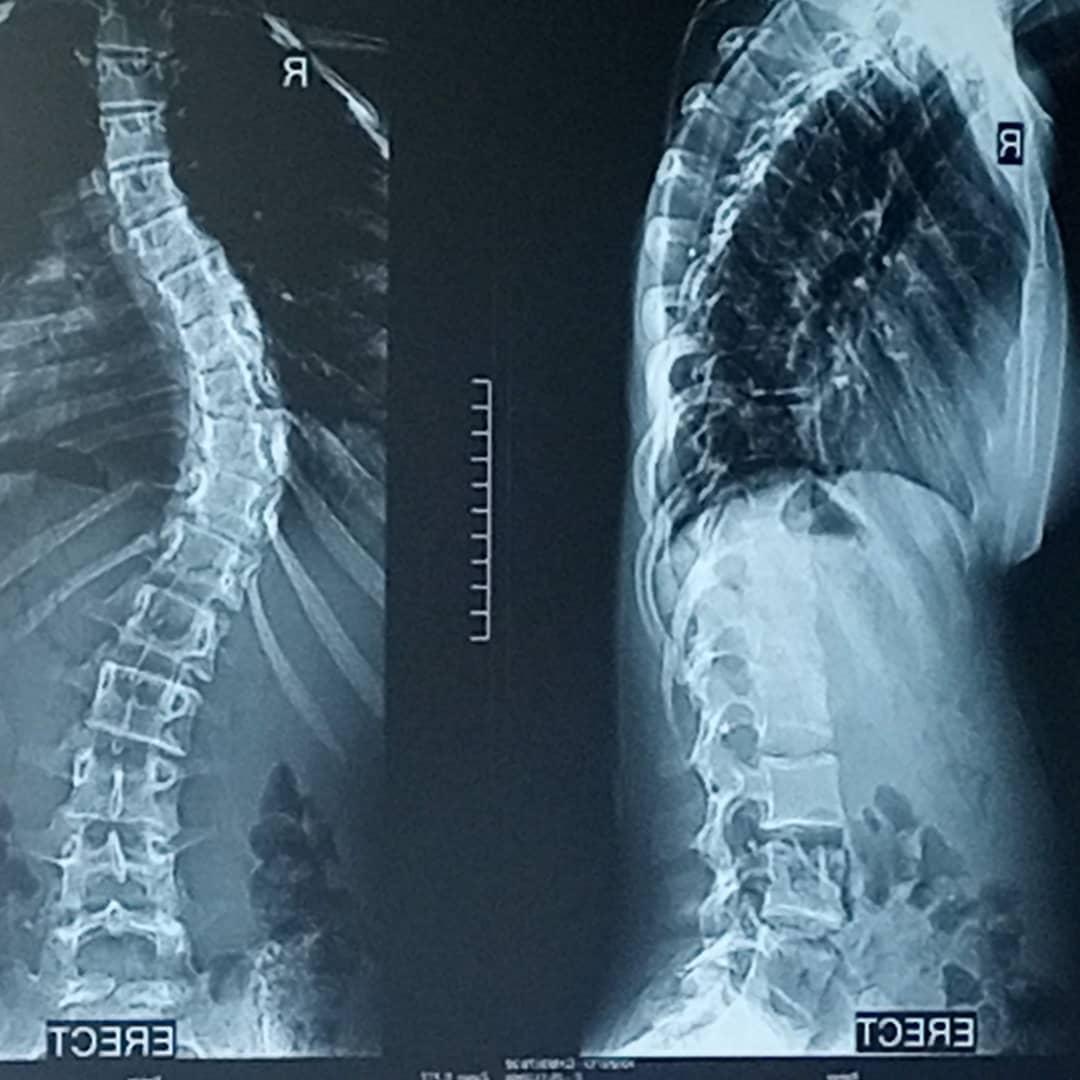

SCOLIOSIS SURGERY FOR CHIAMAKA DIKE

She was diagnosed with scoliosis (deformity of the spin since she was 12 years old and has been living on pain killers to curb the pain

Over the years she has worn boston braces to curb the curve on her spin but to no avail